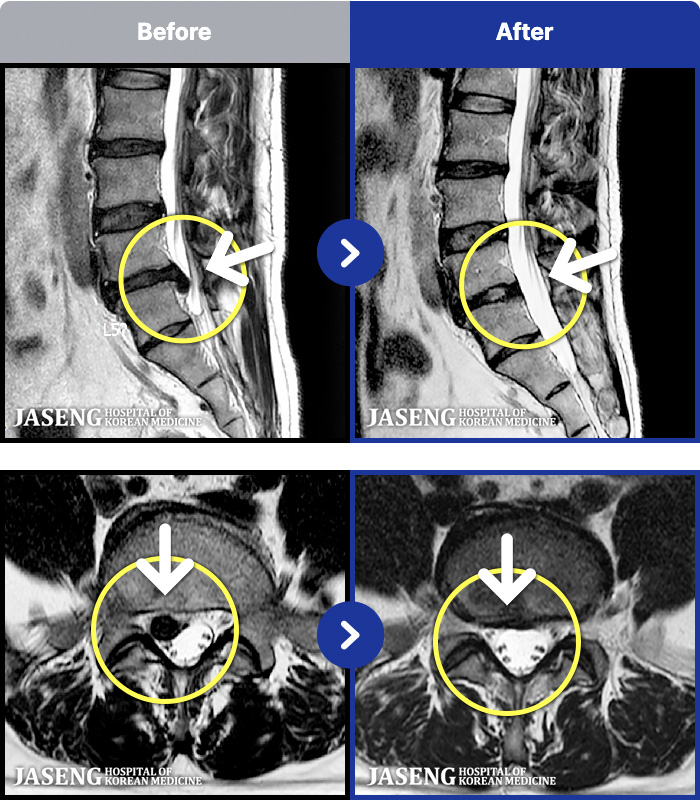

1,257 MRI ũ ʸ Ȯϼ.